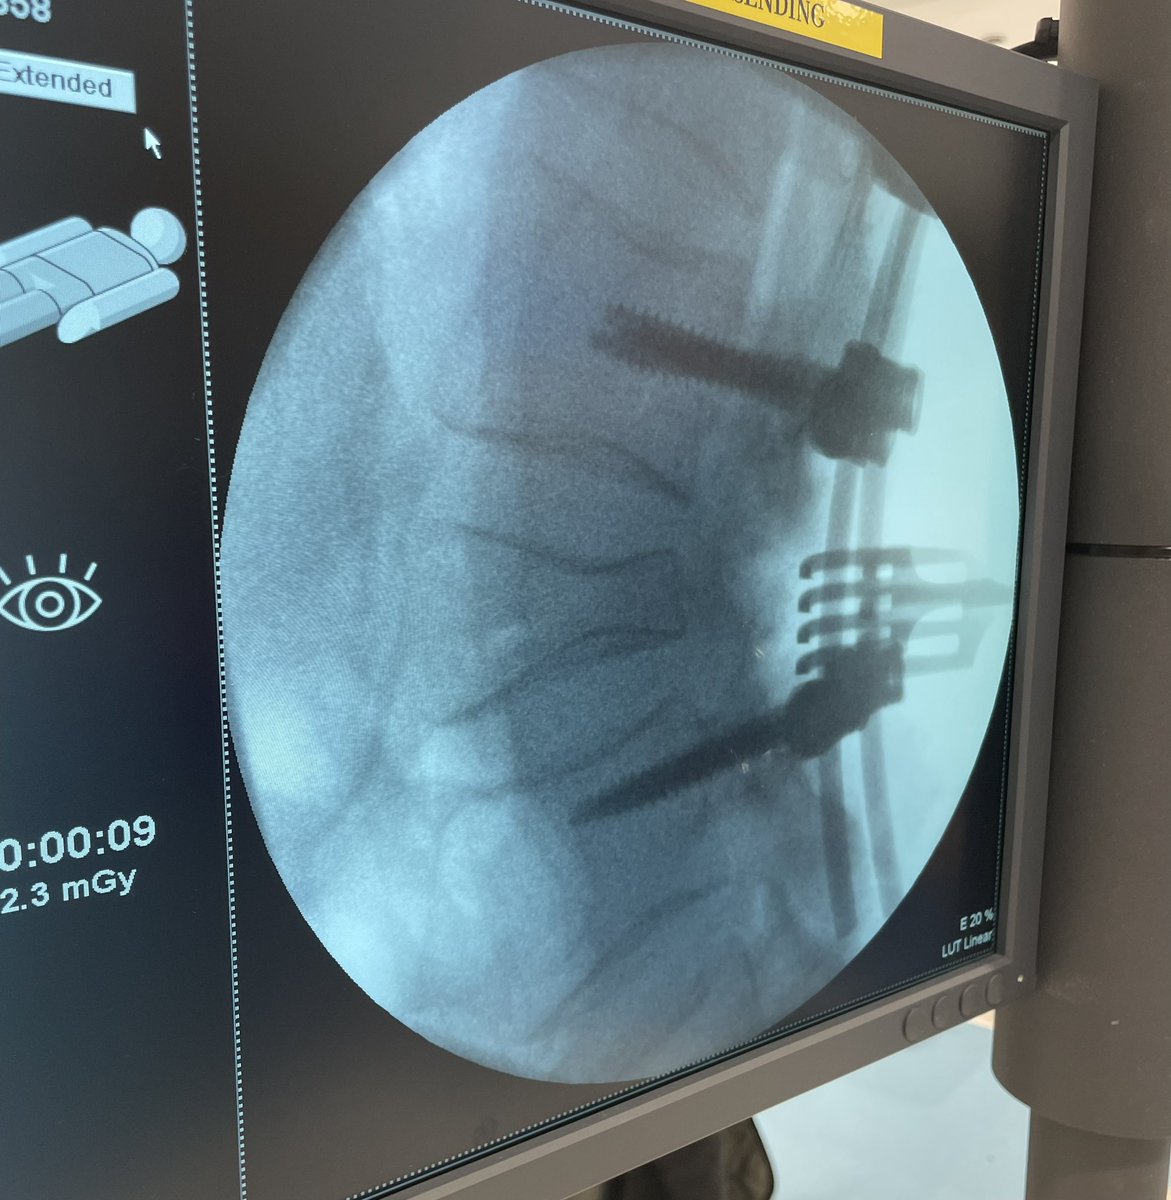

Awake MIS fusion to correct this patient scoliosis. @mayoclinic fellowship @RodNavarroM teaches endoscopic, lateral, MIS awake and deformity. Learn enabling technology & freehand. Accepting fellowship application for 2024-2025. @DoctorQMd @wchrisfox @oakinduroMD @StephenPirrisMD

Pre-and post-op awake MIS fusion to correct this patient scoliosis. @mayoclinic our associate surgeon @RodNavarroMD work hand in hand to learn the latest approach, enabling technology and freehand. Accepting applications for 2024-2025. @DoctorQMd @oakinduroMD @wchrisfox